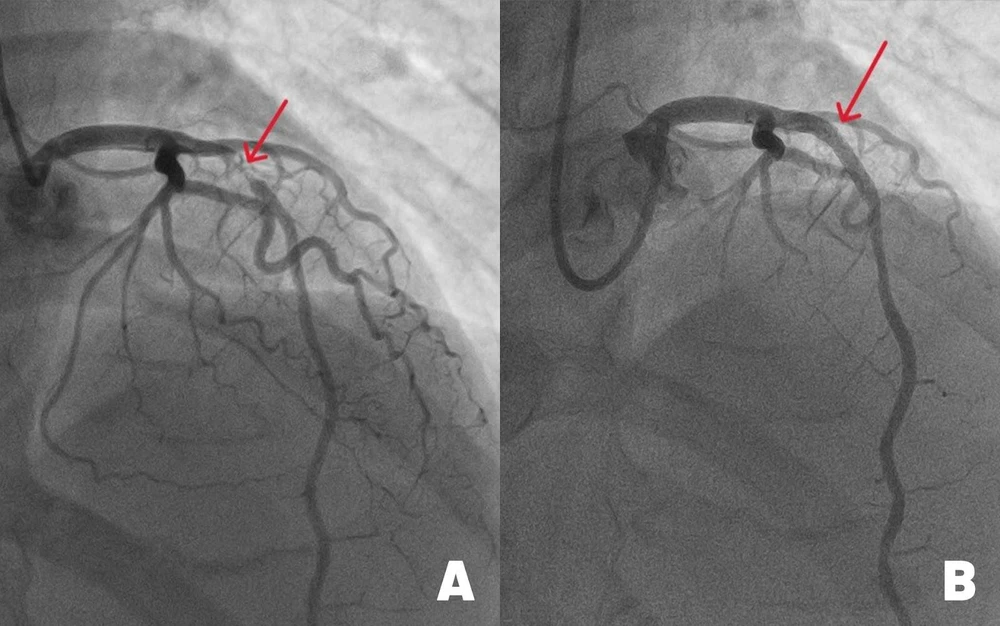

Các bác sĩ Trung tâm Can thiệp mạch BVĐK Tâm Anh TP.HCM đặt stent nong mạch vành hẹp nặng dưới sự hỗ trợ của hệ thống chụp can thiệp mạch (DSA) cánh tay robot xoay 360 độ. Ảnh: BVCC |